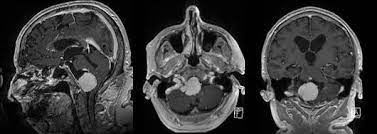

Universitatsklinikum Des Saarlandes Fallbeispiele